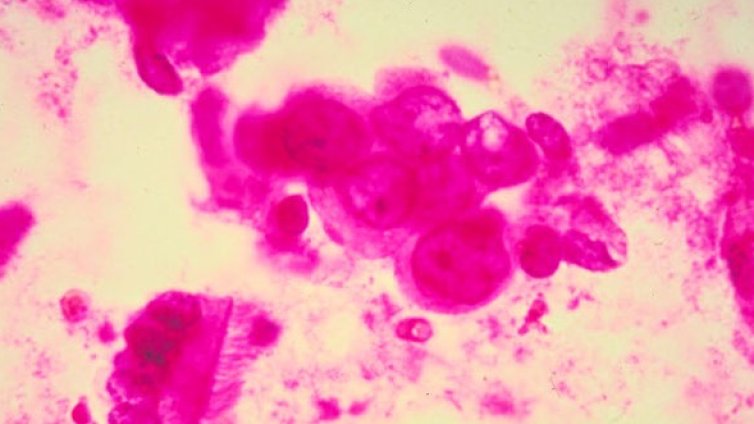

Изследване обяснява как раковите клетки устояват на терапия